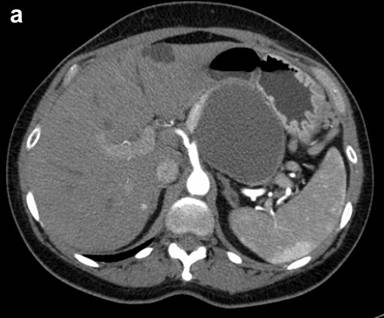

Figure 2. a. CT scan of the abdomen in a 56-year-old female with left upper quadrant pain demonstrates a unilocular pancreatic tail cyst. The cyst wall has variable thickness but does not demonstrate any nodularity. No solid mass was noted. Pseudocyst was suggested in the differential diagnosis of this lesion. b. EUS appearance of the same cyst in A. Thick mucoid cyst content appears granulated on ultrasound, but no visible septations or solid lesions demonstrated. c. Gross surgical resection specimen for the same patient (distal pancreatectomy with splenectomy). No malignancy was detected in this specimen. d. Photomicrograph of a mucinous cystadenoma (H&E, 400x). Columnar mucinous epithelial cells are seen overly ovarian stroma, which is a hallmark of these tumors. |